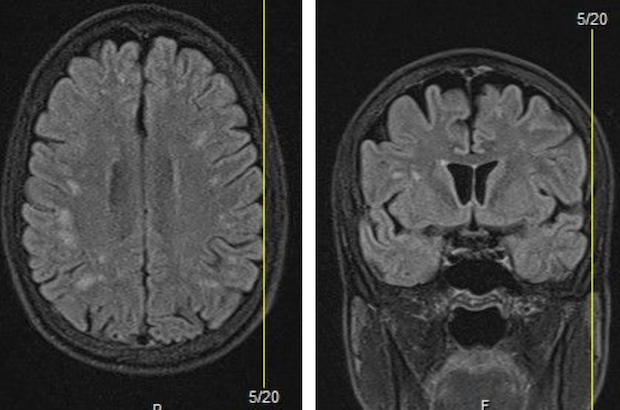

- This 1-hour Grand Rounds session, led by medical neuroradiologist Dr. Steven Veigh, will showcase a series of instructive neuroradiologic images relevant to clinical chiropractic practice. Using real-world imaging cases, Dr. Veigh will highlight key findings that every chiropractic physician should be able to recognize. The session is designed to strengthen diagnostic acumen, improve clinical correlation, and enhance interprofessional communication between chiropractors and radiologists.

- Hour 1 – Principles of neuroradiologic interpretation (CT, MRI, key sequences and planes with case-based review of real-world neuroradiology images relevant to chiropractic physicians.

- Identify common and critical neuroradiologic findings relevant to chiropractic clinical practice.

- Differentiate between benign degenerative imaging findings and red flag pathologies requiring referral.